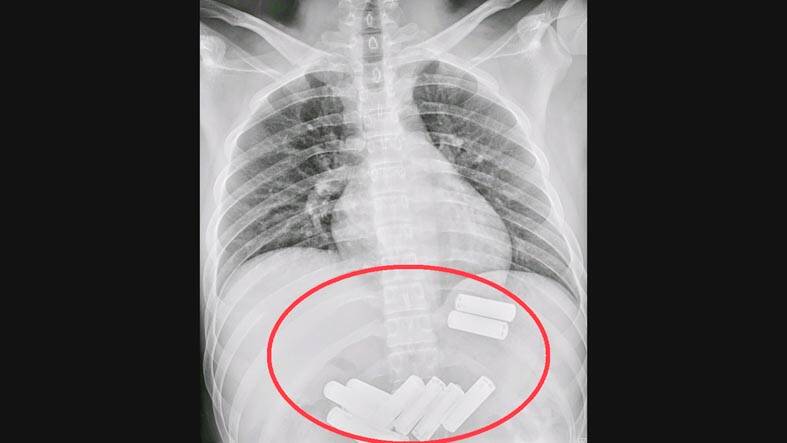

Çin'de bir kişinin yuttuğu 11 pil, endoskopiyle midesinden çıkarıldı

Ankara, 26 Temmuz 23 (TAK): Çin'in Miaoli bölgesinde doktorlar, bir kişinin yuttuğu 11 kalem pili endoskopi yöntemiyle midesinden çıkardı.